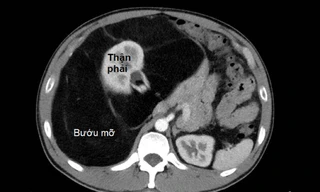

TPO - Bệnh nhân nam 47 tuổi đã phải sống trong tình trạng “bụng mang dạ chửa” suốt nhiều năm vì nhầm tưởng vòng bụng ngày càng lớn là do bia rượu và công việc lái xe đường dài. Đến khi bụng căng cứng, đau tức, ông tới bệnh viện kiểm tra mới biết có khối bướu mỡ khổng lồ đang đe dọa tính mạng.